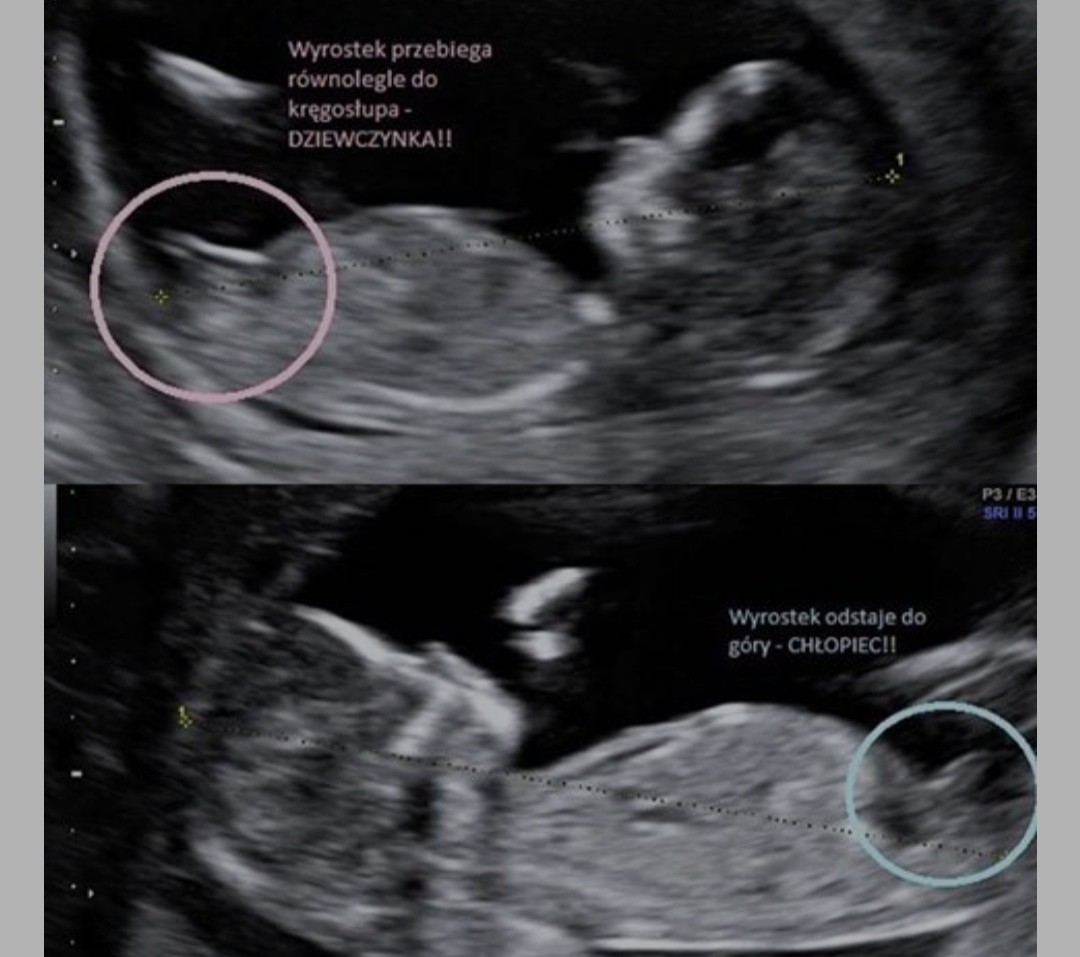

Lekarzem nie jestem, ale jeśli to wyrostek płciowy na usg to mama ginekolog fajnie to opisuje na swoim blogu jak można poznać płeć

IMG_20220619_232137.jpg

Między innymi te zdjęcie. Rzecz biorąc nastawiłam się na dziewczynkę, i takie wewnętrzne przeczucie o tym świadczy a z tych zdjęć wydaje mi się że będzie chłopak . Choć jak wiadomo pewność co do płci okaże się w późniejszym okresie.